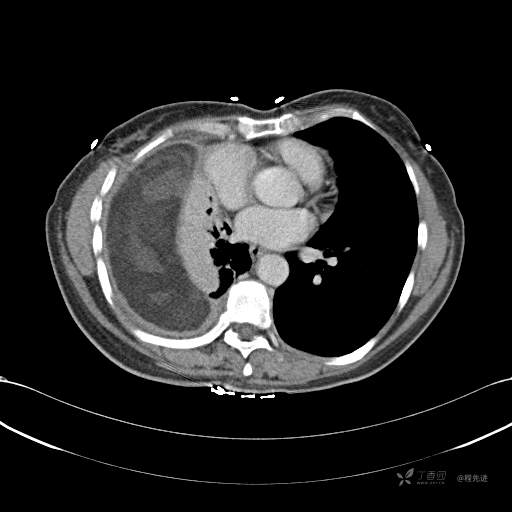

患者性别:女

患者年龄:51岁

简要病史:胸闷半年

肺淋巴管肌瘤病 (7)

乳糜胸 (8)